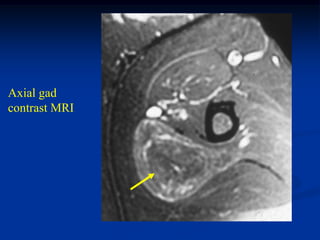

Case #1204 22 yearmale with hemangioma anterior compartment leg with subadjacent cortical hypertrophy of tibia

• 327.

• 328.